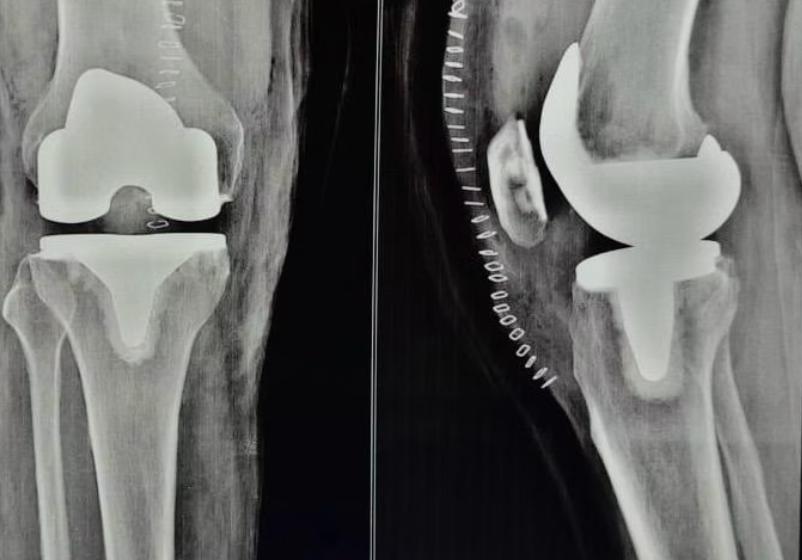

Implantation of Prosthetic Components

The artificial knee parts, usually made of metal and plastic, are implanted. These components mimic the natural movement of the knee.